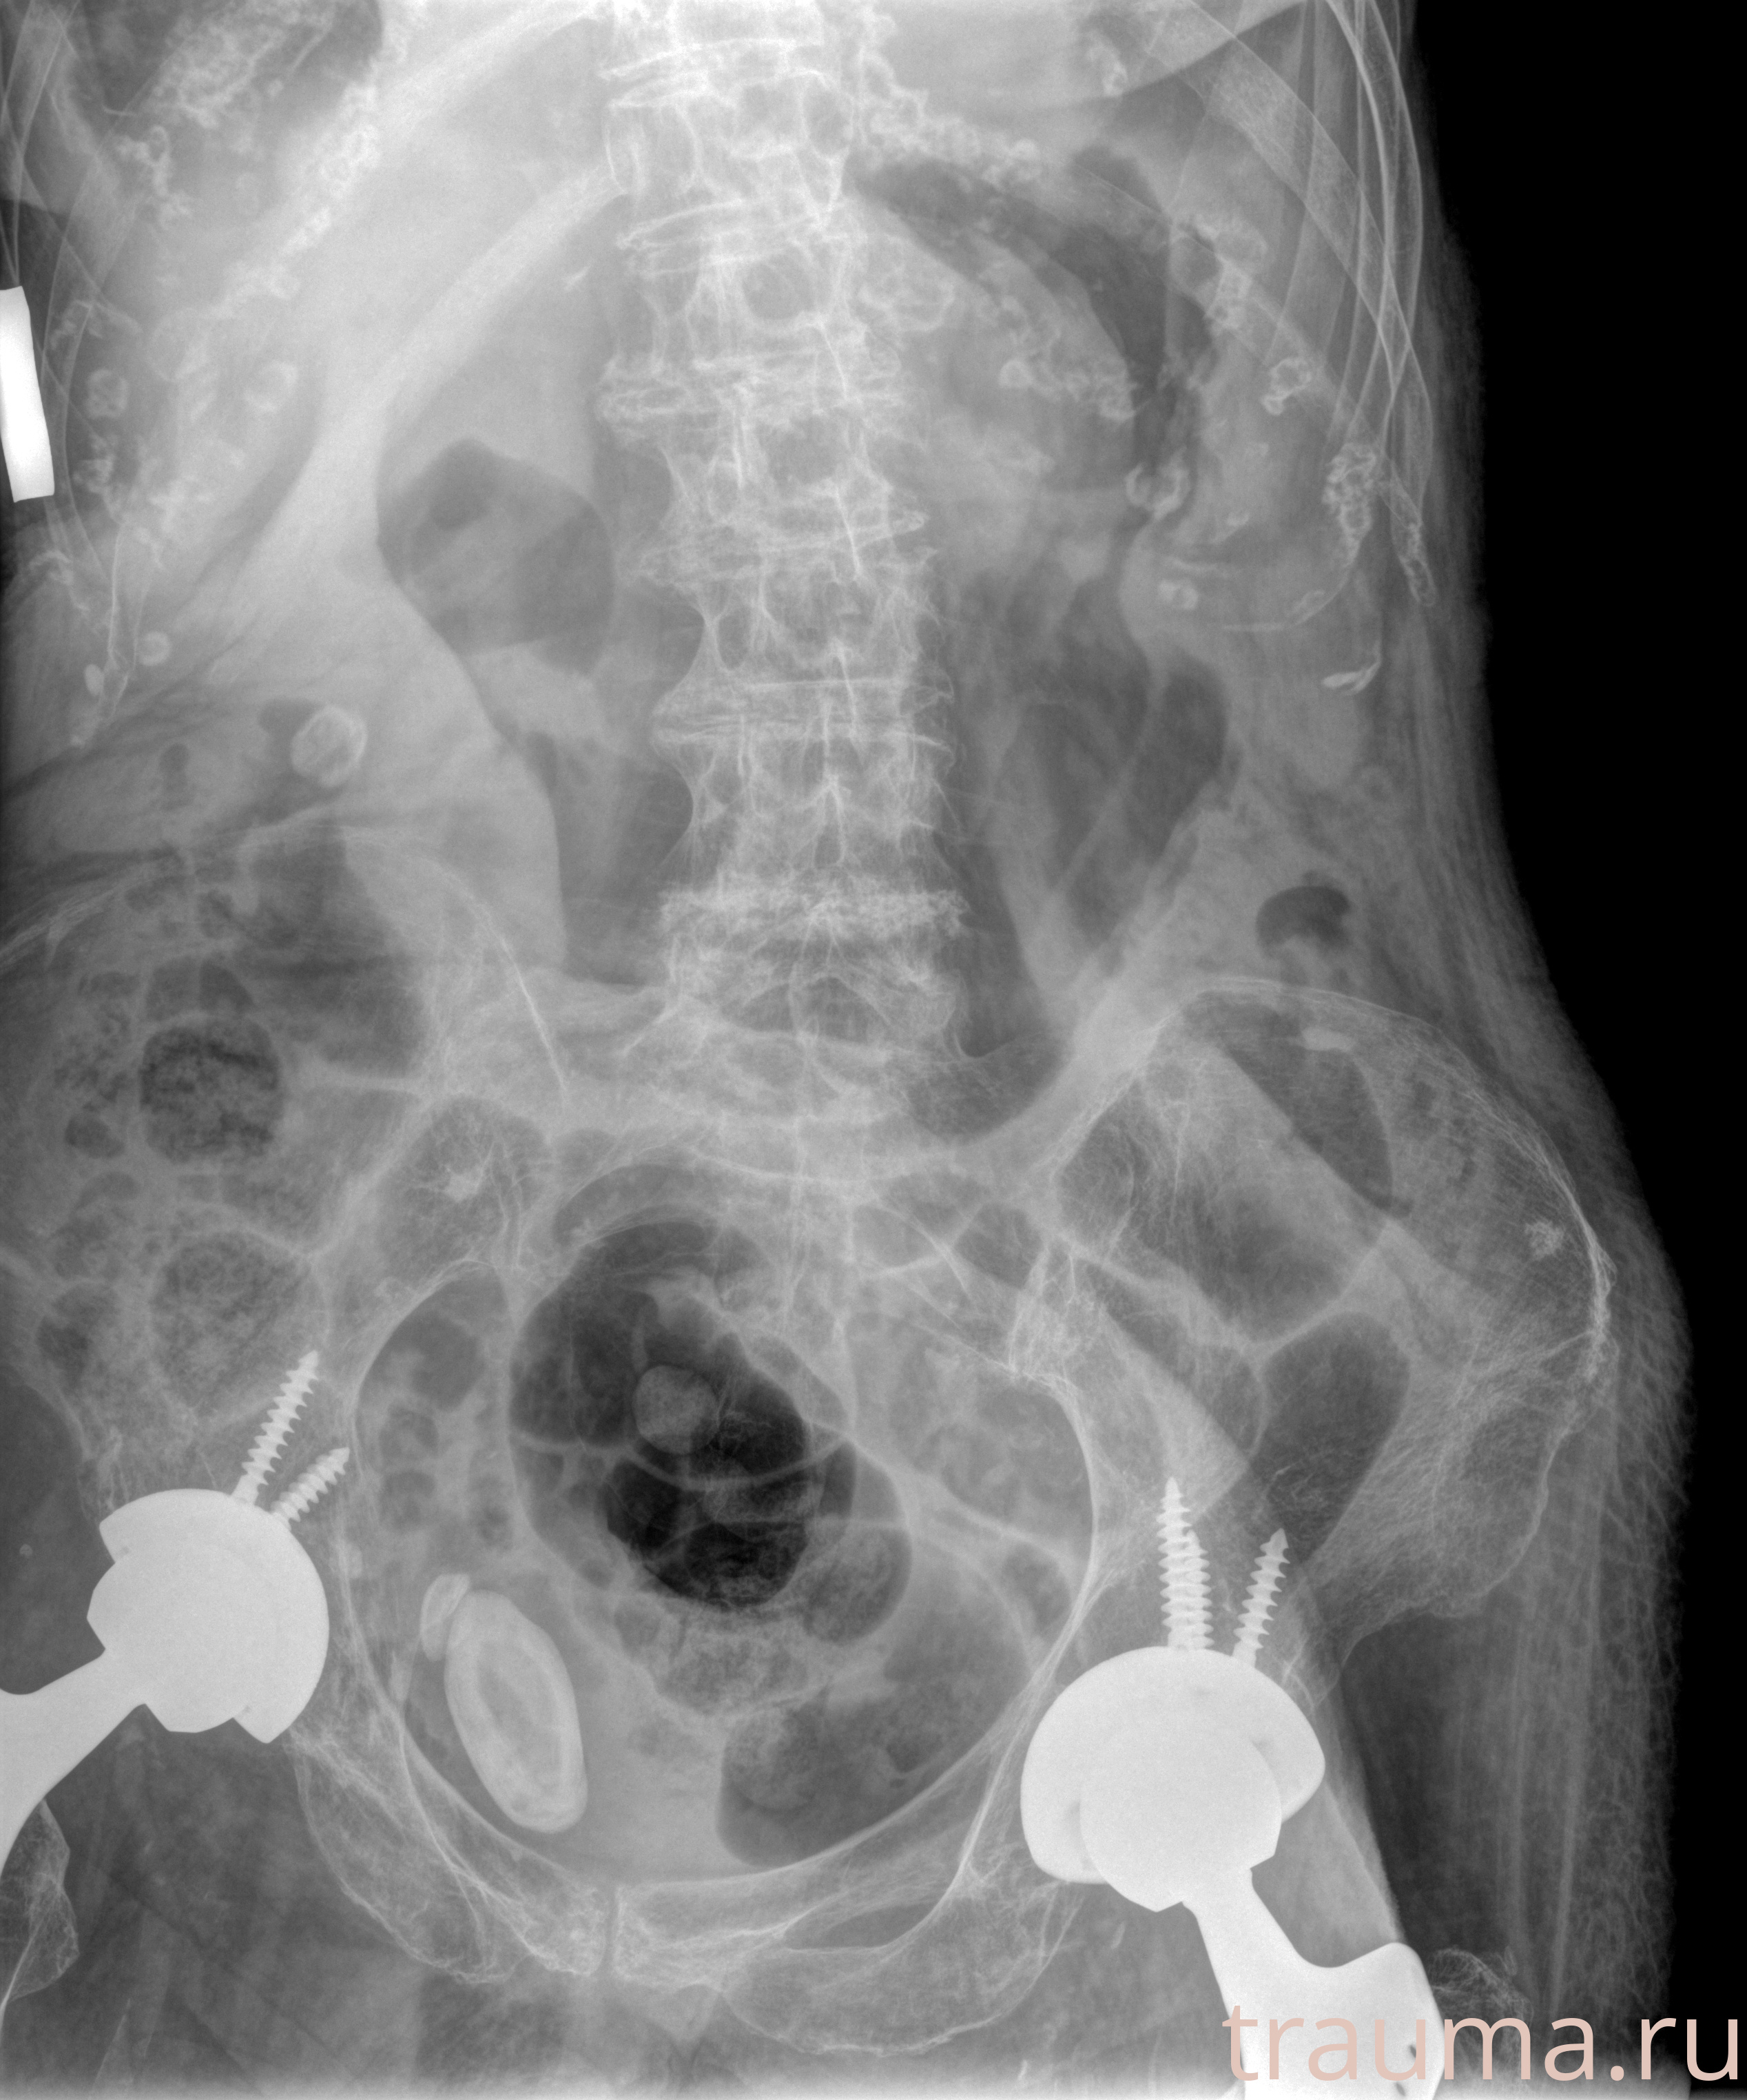

Рентген на дому: по вашему адресу приезжает врач-рентгенолог, травматолог-ортопед с мобильным рентгеновским аппаратом, проводит диагностику травмы или заболевания, делает необходимые рентгенограммы, дает рекомендации по дальнейшему лечению. Получить качественные снимки в домашних условиях возможно благодаря уникальной методике, разработанной МосРентген Центром для института  Склифосовского

при переломе шейки бедра и пневмонии от компании МосРентген Центр - партнера Института имени Склифосовского